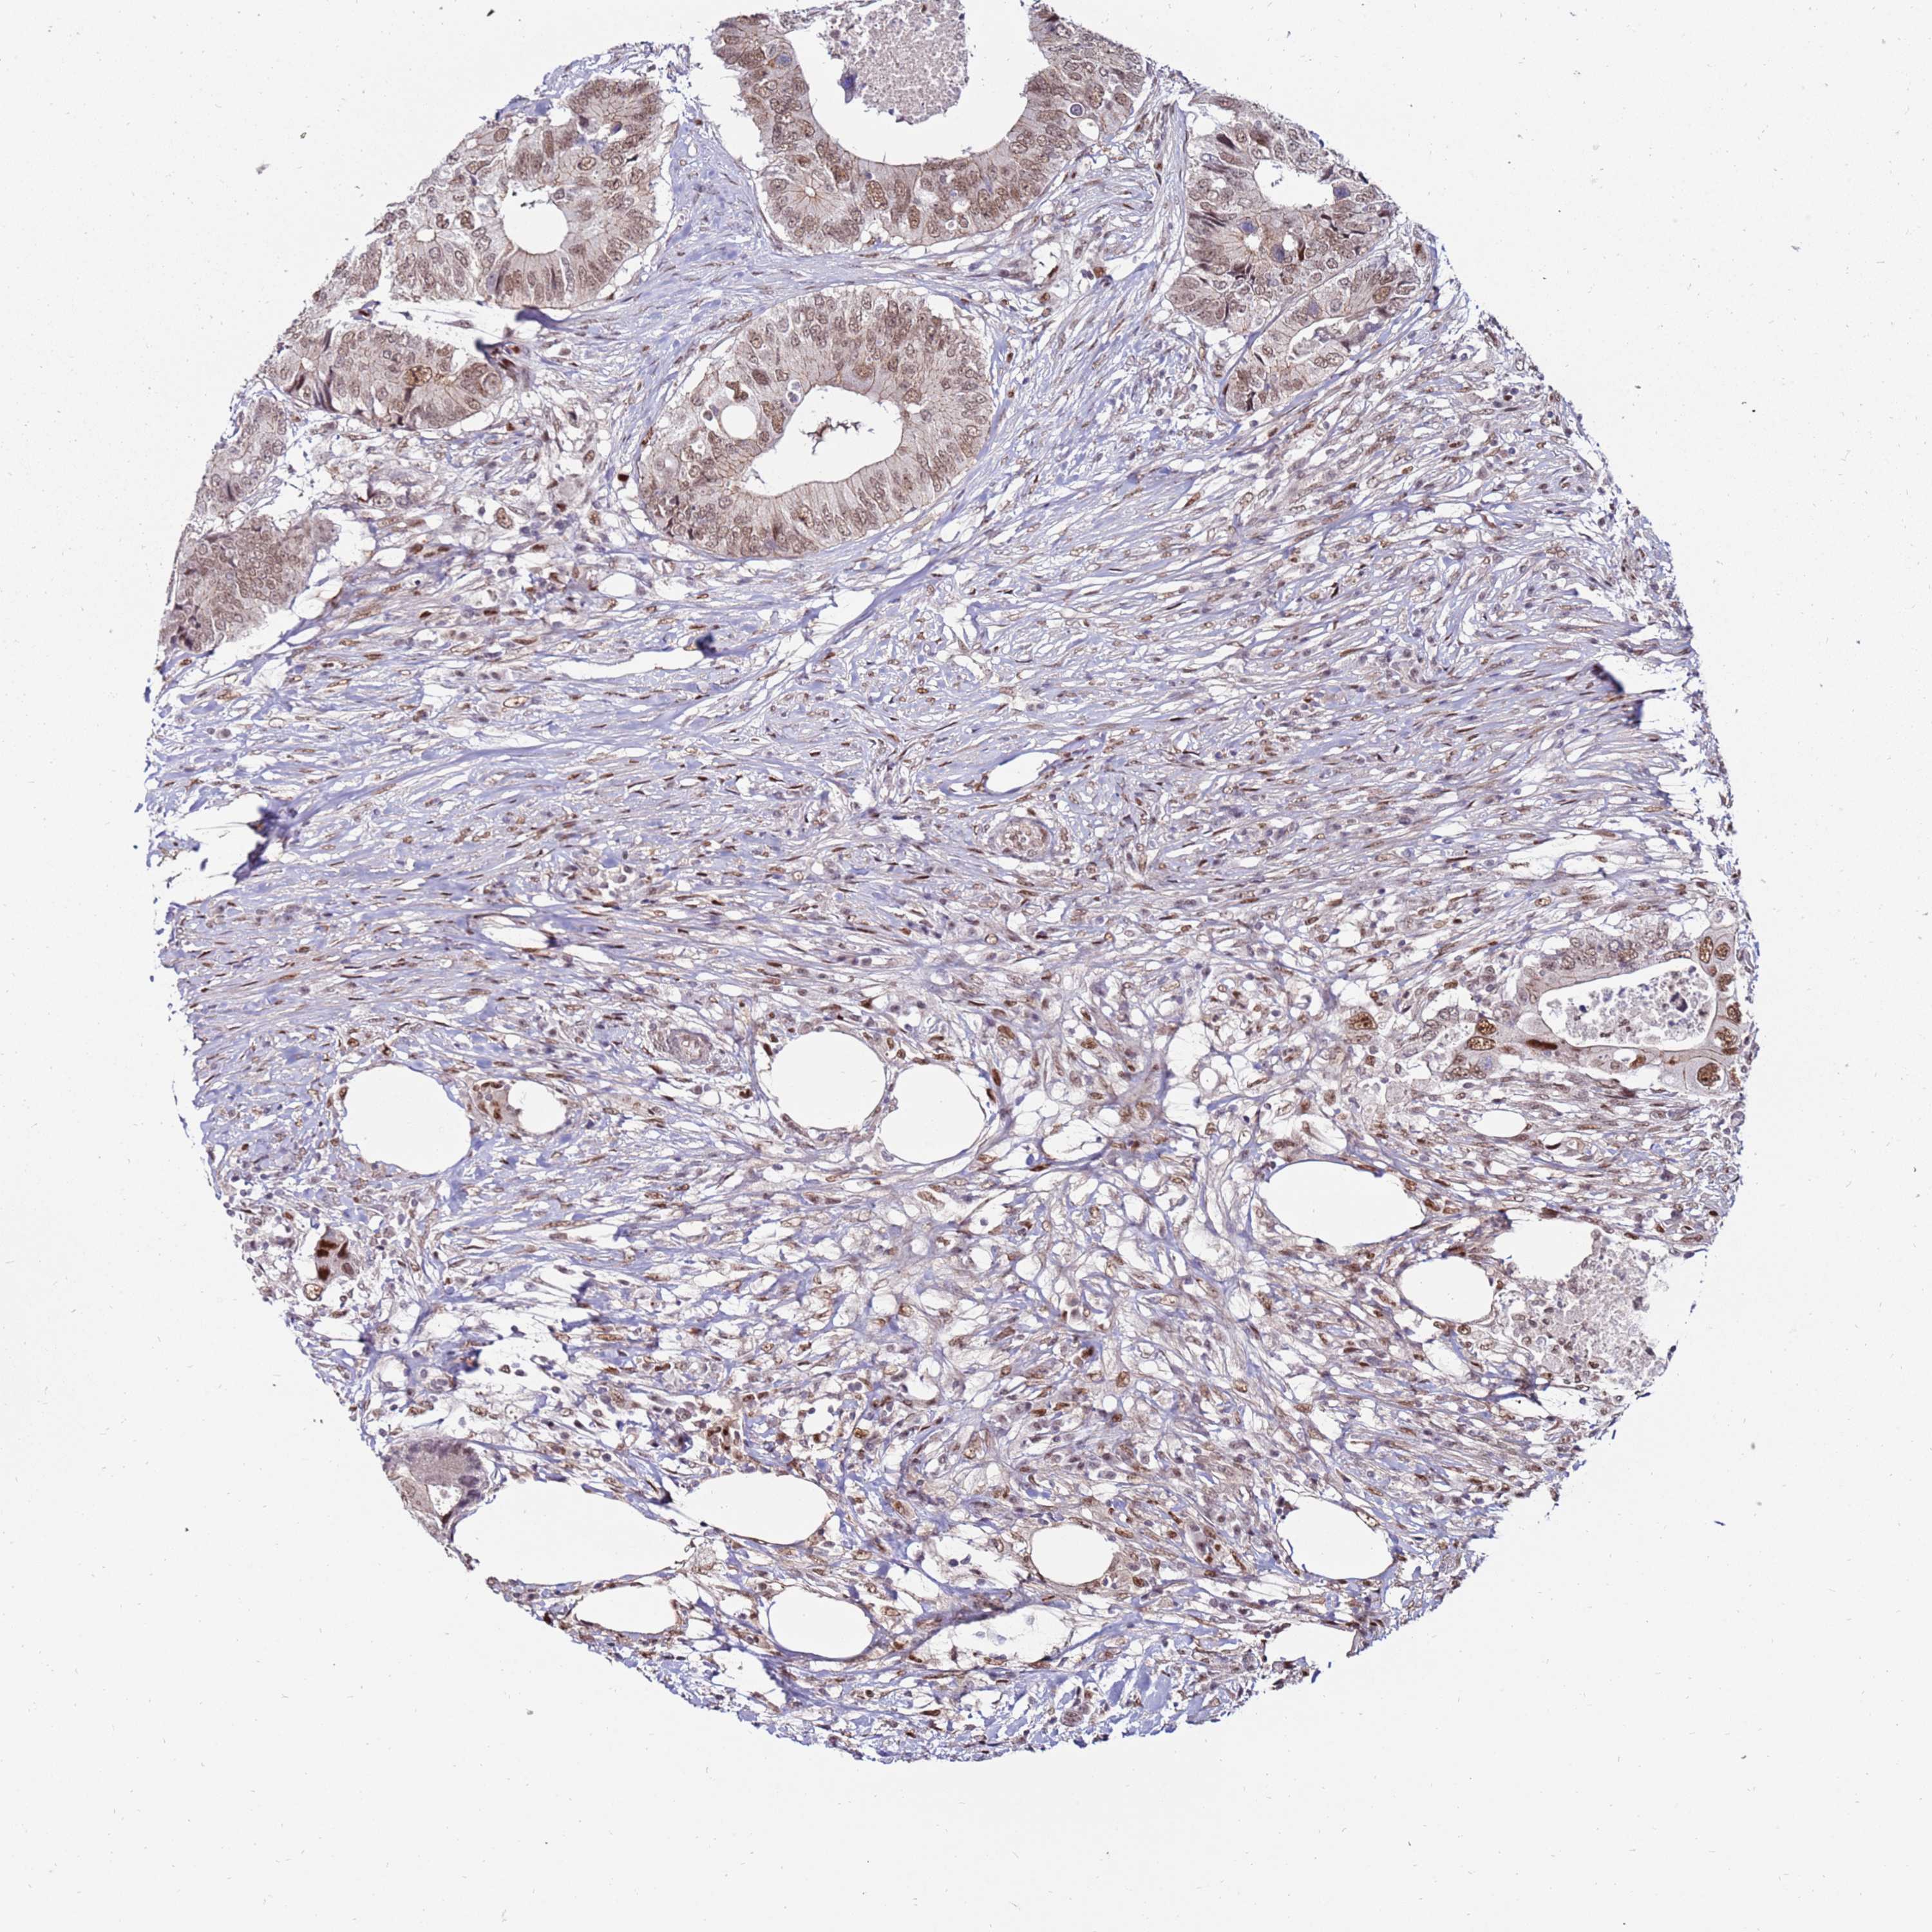

CANCER COLORECTAL CANCER Show tissue menu

Colorectal cancer

Human cancer

Colon adenocarcinoma

Rectum adenocarcinoma